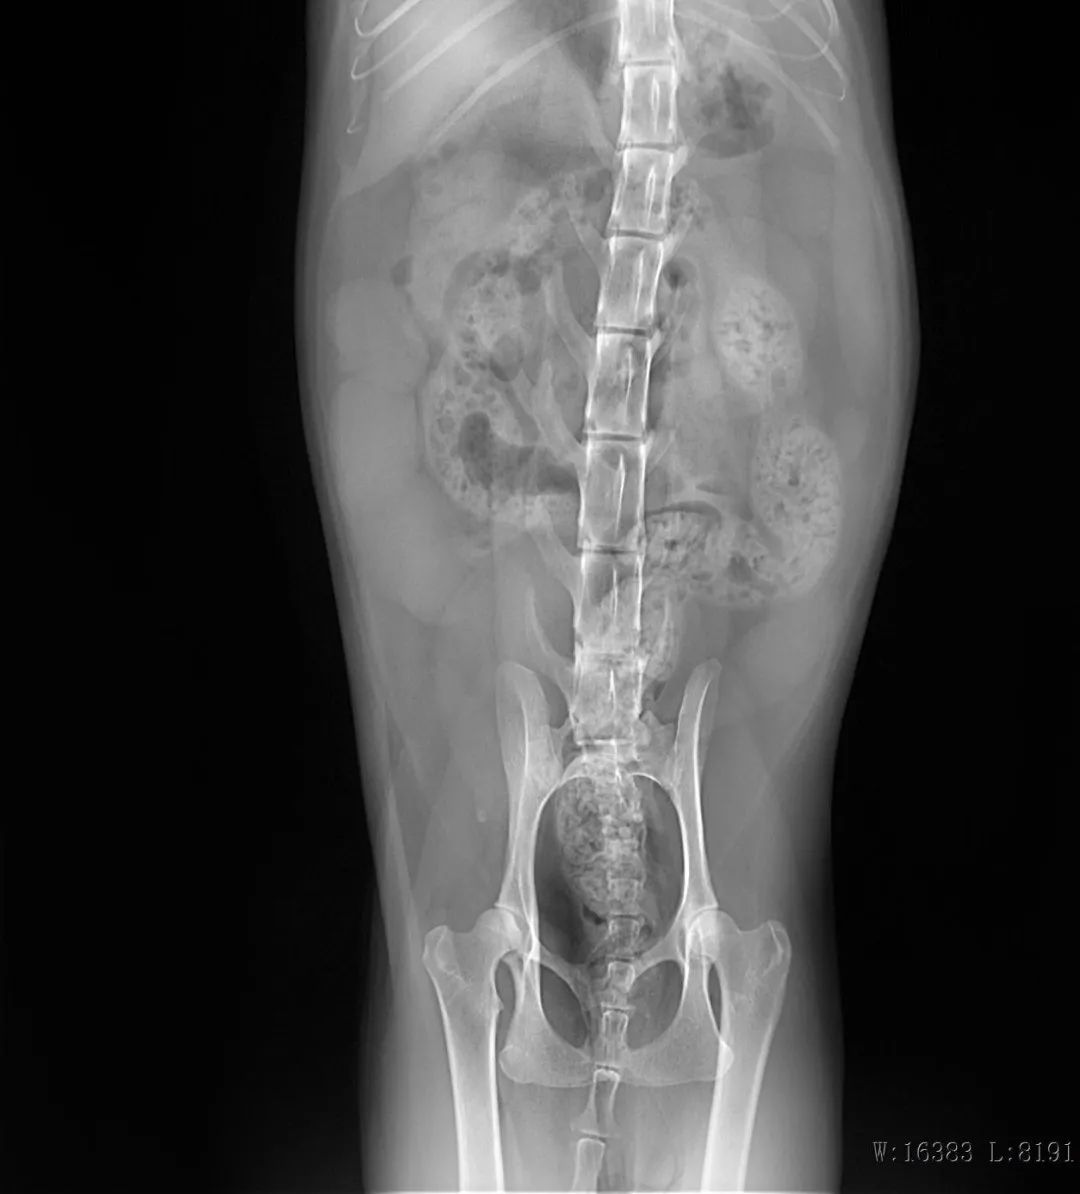

DR检查

B超检查

猫糖尿病、子宫蓄脓感染